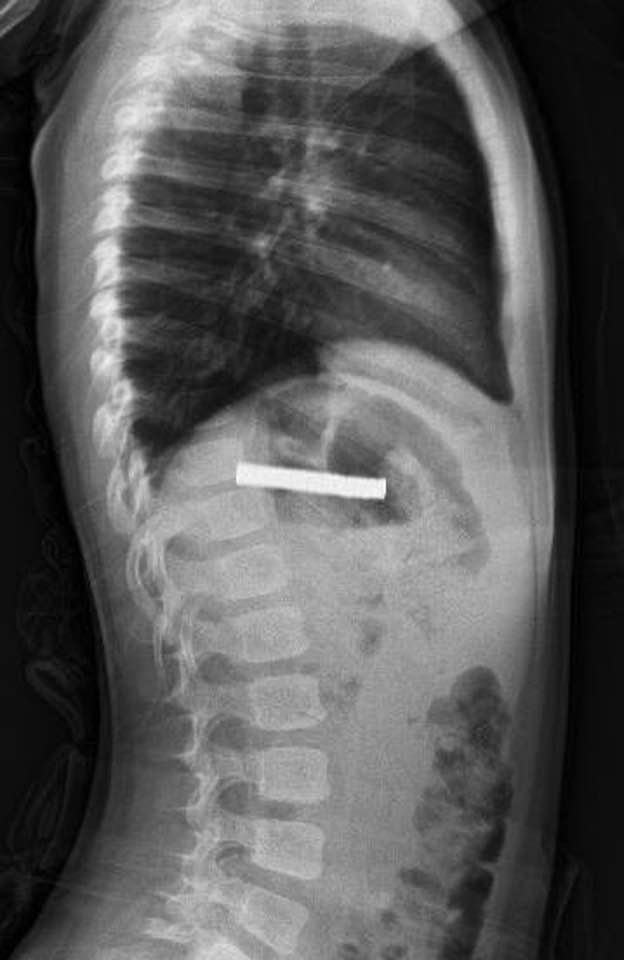

FÜ Çocuk Gastroenteroloji Hepatoloji ve Beslenme Bilim Dalı Başkanı Prof. Dr. Yaşar Doğan’ın yaptığı incelemede, mıknatısların birbirine yapışarak çocuğun yemek borusunu tıkadığı belirlendi. Doğan ve ekibinin gerçekleştirdiği operasyonla mıknatıslar başarılı şekilde çıkarıldı.

Prof. Dr. Doğan, mıknatısların uzun süre yemek borusunda kalması nedeniyle bazı hasarlar oluştuğunu, işlemin kolaylaşması için mıknatısların önce mideye alınıp buradan özel bir file yardımıyla çıkarıldığını belirtti. Çocuğun bir gece gözlem altında tutulduğunu, genel durumu iyi olduğu için ertesi gün taburcu edildiğini aktardı.